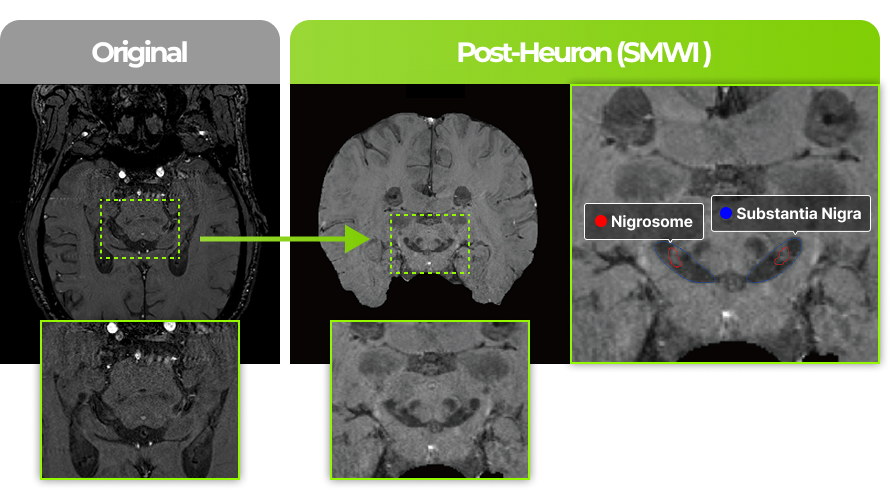

Assists in the diagnosis of Parkinson’s disease

by analyzing and quantifying on brain MRI.